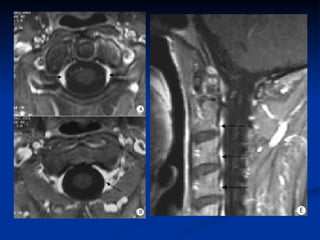

IRM dorsale  coupes  : une acquisition de repérage est réalisée dans un plan frontal  plans de coupe:  plan sagittal objectivant l'ensemble du rachis plan axial transverse pour une étude segmentaire épaisseur de coupe ne doit pas dépasser 3 à 4 mm dans le plan sagittal et 5 à 10 mm dans le plan axial

IRM dorsale Un examen IRM du rachis thoracique comprend le plus souvent : une séquence pondérée en T1, avec des coupes fines (3 à 4 mm) dans un plan sagittal  une séquence pondérée en T2 dans le plan sagittal ;  si besoin, des coupes axiales pondérées T1 ou T2 suivant l'indication.

IRM dorsale Unexamen IRM du rachis thoracique comprend le plus souvent : une séquence pondérée en T1, avec des coupes fines (3 à 4 mm) dans un plan sagittal une séquence pondérée en T2 dans le plan sagittal ; si besoin, des coupes axiales pondérées T1 ou T2 suivant l'indication.